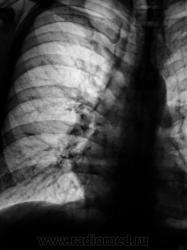

Рентгенограмма в прямой проекции.

такое впечатлени, что бронх окутан муфтой..

Да, вроде-бы и некоторая гиповентиляция правого лёгкого имеет место быть?

но какаято это муфта не агресивная..еще смутила деформация и сгущение рисункаюю Валентин Львович, а что в архиве?

"флюшка" за 2009 г. - "норма".